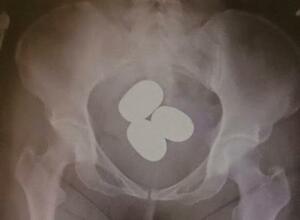

東京税関成田税関支署が公表した、香港からの旅客が体内に粉状の金を隠し密輸しようとした摘発事例(同署提供)

東京税関成田税関支署は24日、粉状の金を避妊具などに入れて体内に隠し、香港から成田空港へ密輸するケースが急増していると明らかにした。今年1~3月に押収しただけで時価総額は約12億円に上る。不安定な国...